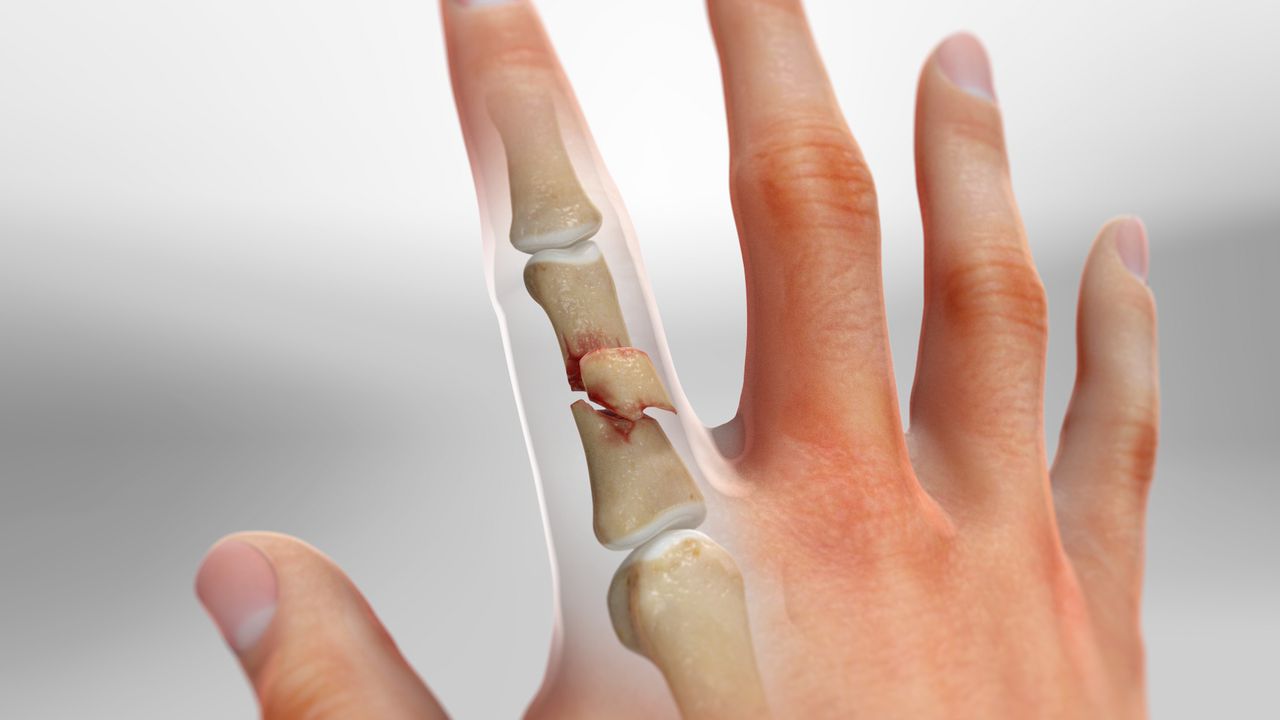

골절의 종류와 치료 방법

손가락 뼈에 금이 간 경우, 그 정도에 따라 치료 방법이 달라질 수 있습니다.

- 단순 골절: 뼈가 깨지지 않고 비교적 완만하게 금이 간 경우에는 깁스로 고정해주기만 해도 충분할 수 있습니다.

- 복합 골절: 뼈가 여러 조각으로 깨져 있는 경우에는 핀이나 금속판을 사용하여 뼈를 고정해야 할 수 있습니다.

- 비스듬한 골절: 뼈가 비스듬하게 부러진 경우에도 핀을 사용하여 고정하는 것이 일반적입니다.